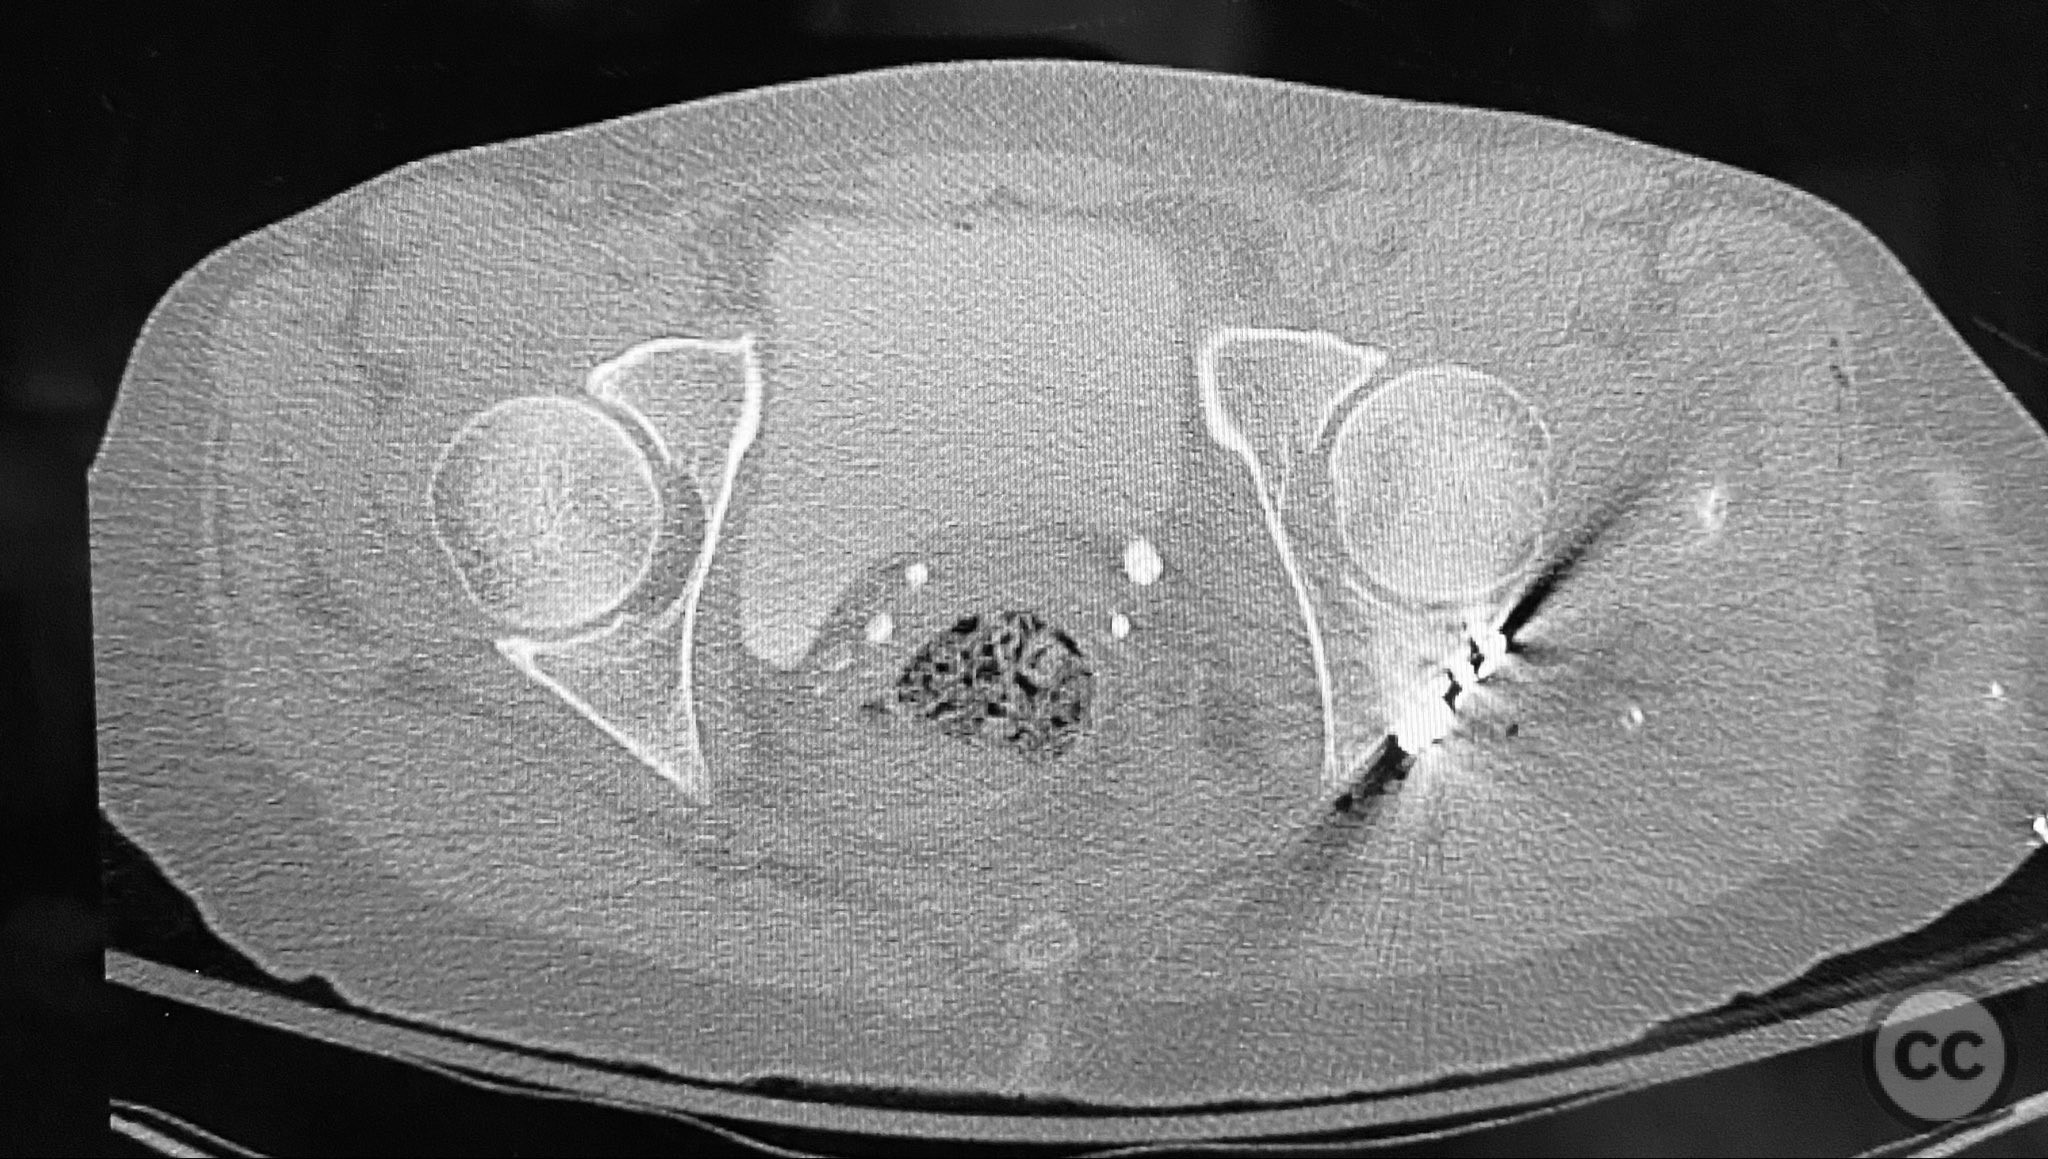

Clinical and radiological findings:  A patient sustained a posterior wall acetabular fracture-dislocation, characterized by comminution of the posterior wall, impaction of fragments into the posterior column region, and intra-articular loose fragments within the fossa acetabuli. Sagittal imaging demonstrated femoral head impalement on the intact wall, raising concern for potential irreducibility. Coronal and axial CT images revealed acetabular and femoral head impactions, peripheral wall comminution, incomplete fracture extension at the acetabular notch and quadrilateral surface, and an articular fragment within the joint. Surface renderings confirmed the extent of peripheral wall comminution and impaction. Despite these findings, a closed manipulative reduction was successfully achieved, resulting in a congruent reduction on post-reduction imaging.

Planning remarks:  The preoperative plan included a prone Kocher-Langenbeck (KL) approach to the acetabulum. The plan involved application of a distractor to facilitate removal of intra-articular loose fragments, elevation of impacted articular segments, bone grafting of resultant defects with ground allograft, and stabilization of the posterior wall with multiple plates, including a custom spring hook plate for peripheral fragment support.

The injury demonstrated extensive comminution and impaction of the posterior wall with intra-articular debris requiring meticulous removal and elevation. The use of a distractor facilitated both exposure and removal of loose articular fragments. The peripheral comminution necessitated augmentation with a custom spring hook plate to maintain reduction of small cortical fragments not amenable to standard buttress plating. Proper placement of the lateral reconstruction plate overlying the spring hook plate was critical for maintaining fixation integrity; malpositioning resulted in early fixation failure in a comparative case due to bending of the unsupported spring hook implant.